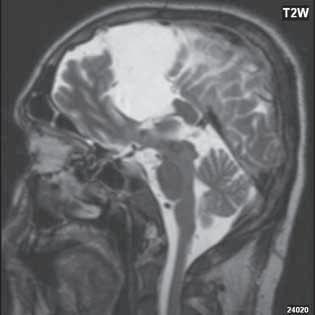

Obr. I.1.2a Paralelní postavení postranních komor, kolpocefalie, ageneze corpus callosum

Obr. I.1.2b Ageneze corpus callosum

Při agenezi corpus callosum CT i MR zobrazí paralelní průběh postranních mozkových komor (oproti fyziologickému

konvergentnímu průběhu) a jejich oddálení, časté rozšíření okcipitálních rohů – colpocefalie, někdy středočárový lipom, cystu. Koronální řezy ukážou rozšíření frontálních rohů postranních komor, III. komora je situována vysoko mezi postranní komory, tvoří jakoby trojzubec, který někteří autoři přirovnávají k přilbě Vikinga. Není patrné septum pellucidum. Častá je přítomnost středočárového lipomu nebo cysty.

Na vnitřní straně postranních komor pozorujeme v T2W obrazu poněkud tmavší strukturu než okolní myelinizovaná vlákna (naopak v T1W obrazu zvýšený signál), Probstovy provazce, axony, které za fyziologických okolností přecházejí přes corpus callosum do kontralaterální hemisféry.

Sagitální řezy nám přinášejí nejvíce informací o corpus callosum. Pozorujeme radiální průběh mozkových sulků ke stropu III. komory na vnitřní straně mozkových hemisfér a naopak nezobrazíme gyrus cinguli. Při parciální agenezi je postiženo především splenium.